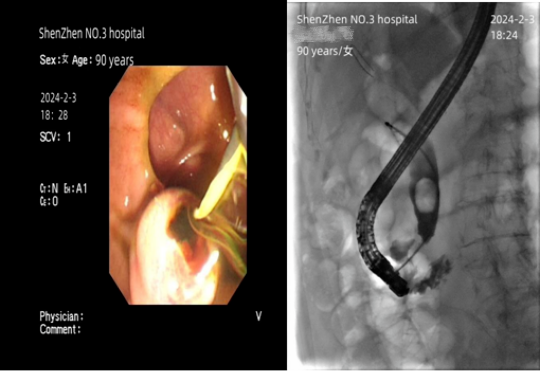

2024年2月3日,高烧3天的郑奶奶(化名)被转到了深圳市第三人民医院(南方科技大学第二附属医院)。刚到急诊时,她已经陷入了半昏迷状态,白细胞计数高达30x10^9g/L(正常值为3.5-9.5x10^9g/L),已处在感染性休克边缘。在深圳市三医院消化内科医护人员的紧急治疗之下,郑奶奶体内的脓液被成功引出,在短暂住院后就可以回家过年团聚了。

ERCP术,即经内镜逆行胰胆管造影术,是微创治疗胆胰疾病的最佳选择。相对开腹手术而言,ERCP术有无需麻醉、创伤小、恢复快的优势,是郑奶奶最适合的治疗方式。对于石德红而言,这台手术有“急”、“难”、“危”特点。

消化内科ERCP团队迎难而上,由从事ERCP术28年之久、临床经验丰富的石德红担任术者,用时仅仅20分钟就完成了手术,从郑奶奶体内抽出200多毫升脓液。“这台ERCP术比平时做得更快,是因为我们要抢时间。”石德红说。